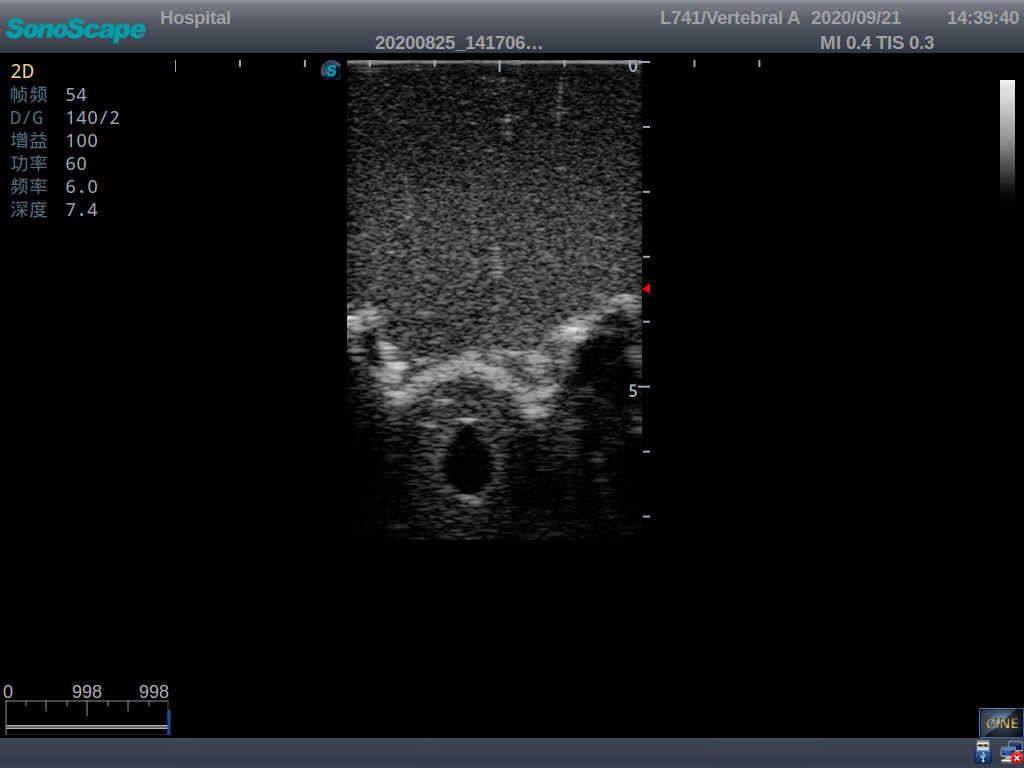

Adult Lumbar Puncture Ultrasound Training Model

Model TYE1549.2

This model is an ideal choice for ultrasound-guided adult lumbar puncture training with true-to-life skin feel and touch, accurate anatomical structures as well as real clinical ultrasound images. Realistic resistance to needle tips and correct landmarks provide excellent hands-on experience.

Accurate anatomical structure of L1-L5 and the vertebral canal

2)  Real clinical ultrasound images

1)   Ultrasound-guided lumbar puncture practice